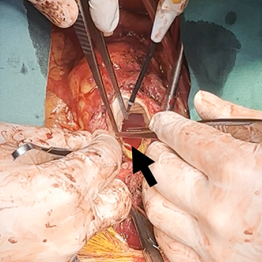

经胸超声心动图提示:人工主动脉瓣可见赘生物(29×9mm,活动度大,且随心动周期显著摆动)(图1);重度瓣周漏;瓣叶撕裂并伴有广泛瓣周脓肿形成。主动脉根部扩张,无冠窦明显膨出,并可见右冠窦至右心房瘘管形成。其余可见严重二尖瓣反流、中度三尖瓣反流及三尖瓣上赘生物附着。

二尖瓣赘生物附着伴严重反流

手术成功完成